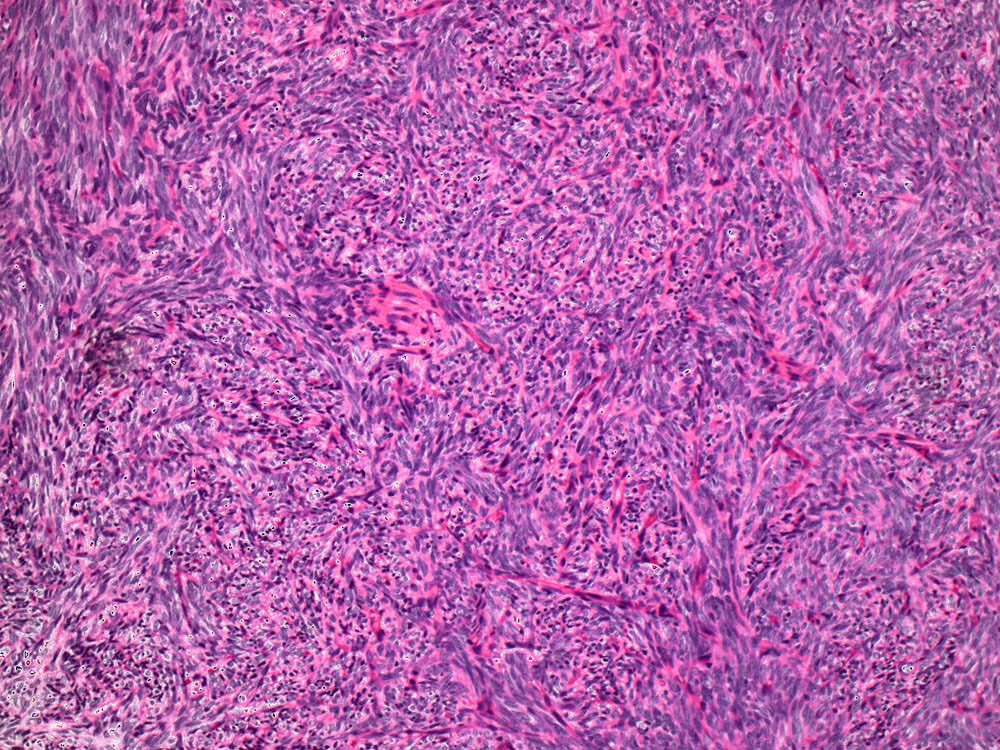

Case: ShoulderMass

Final Diagnosis: